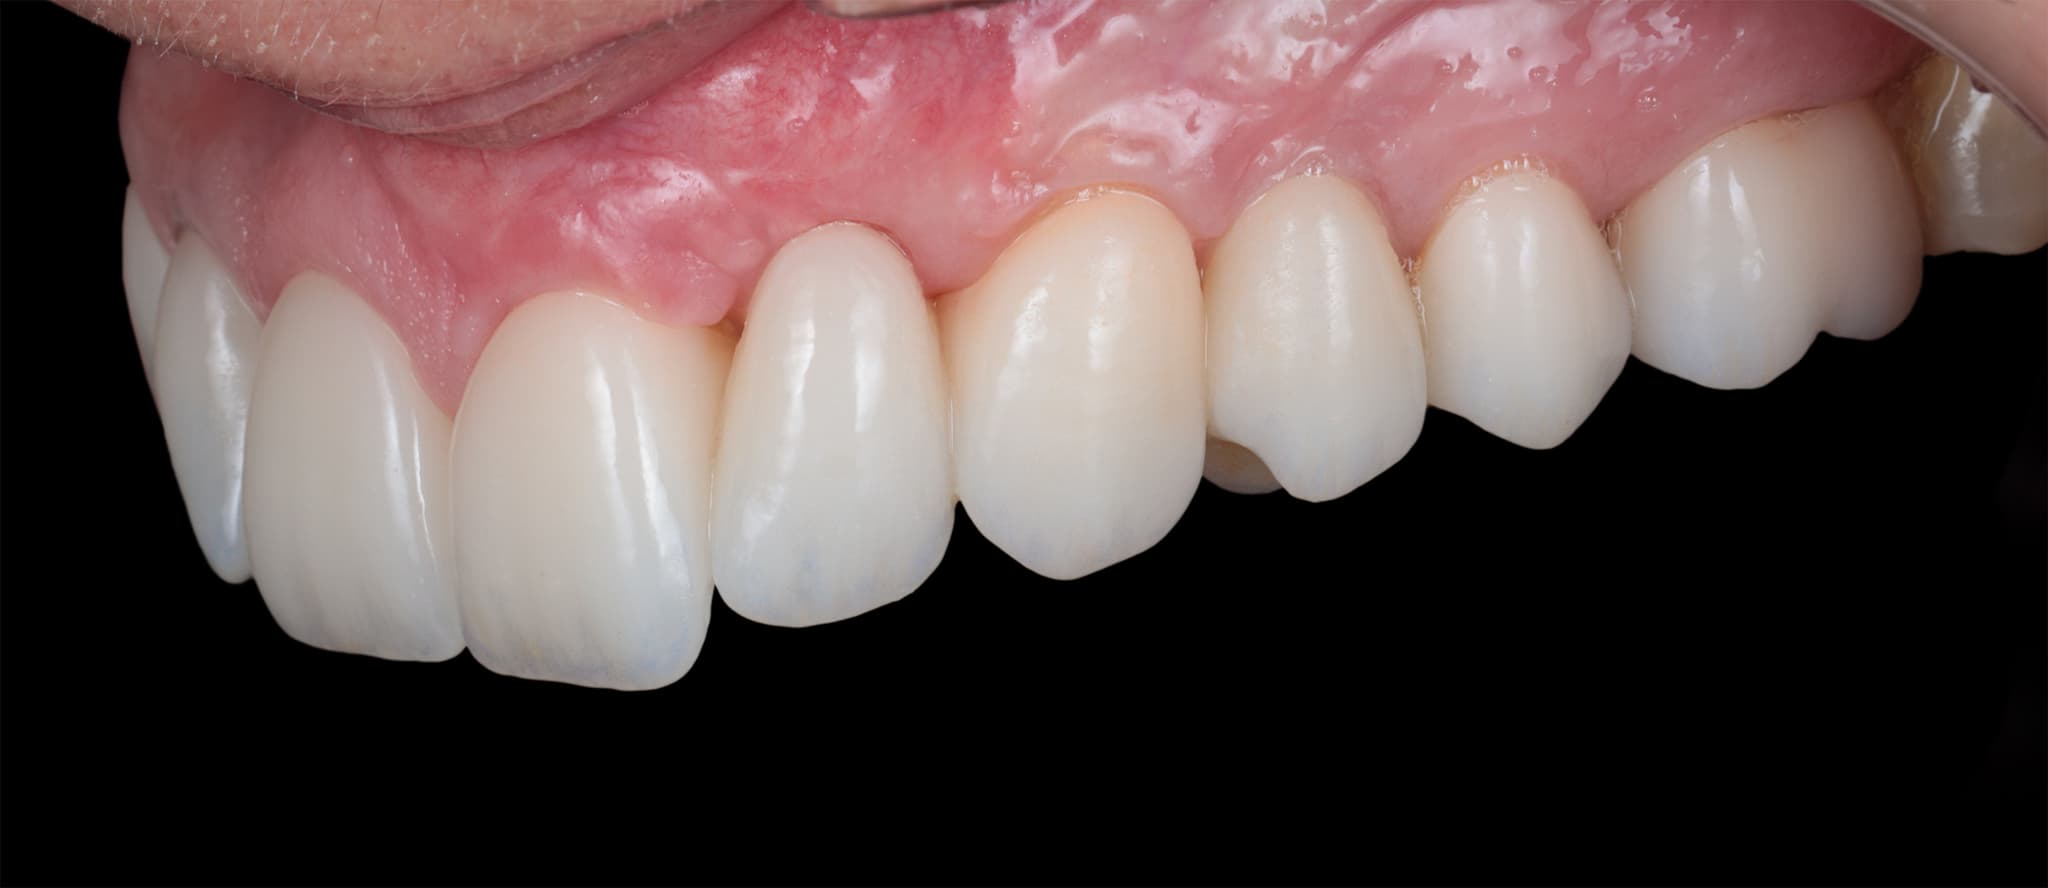

Țesuturi sănătoase pentru estetică naturală.

Rezultatele estetice nu depind doar de ceramică—ci și de sănătatea și conturul țesuturilor moi. De aceea, luăm în considerare arhitectura parodontală încă din faza de design. Modelăm, protejăm și menținem țesuturile moi pentru a susține atât sănătatea, cât și armonia.